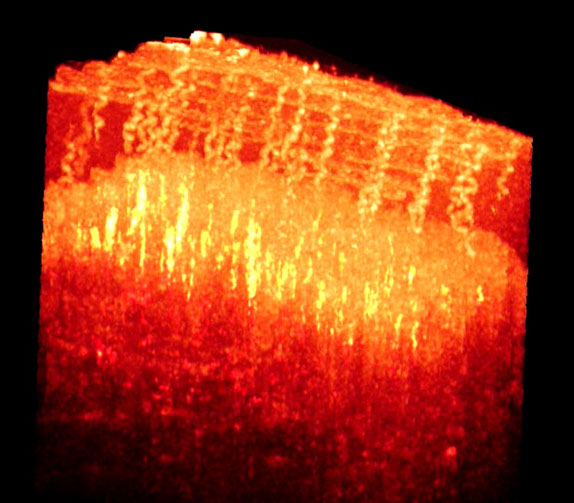

Ultrahigh speed SDOCT (500,000 A-scans per second) provides ability for comprehensive assessment of the retina status over a large field view. (a) 3D rendered volumetric image. (b) to (f) are typical depth resolved fundus (en-face) images, which are corresponding to the depth positions marked by the red, yellow, green, blue and purple lines in (a).